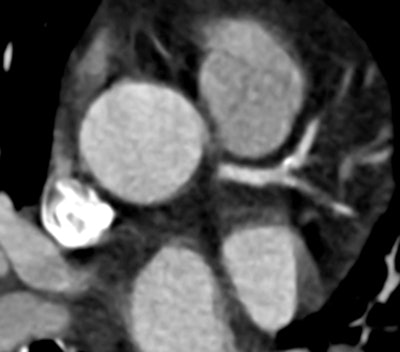

| Compared with filtered back projection reconstruction (above), use of the TRIM algorithm improves temporal resolution and renders a more diagnostic image. Images courtesy of Dr. U Joseph Schoepf, MUSC. |

"Despite cardiac CT image acquisition with slower gantry rotation, the temporal resolution improved reconstruction algorithm evaluated here provided more diagnostically adequate image quality for coronary artery assessment than the standard FBP [filtered back projection] reconstruction algorithm," wrote Dr. Paul Apfaltrer from the University of Heidelberg and MUSC, and colleagues in an article-in-press in the European Journal of Radiology (November 5, 2012).